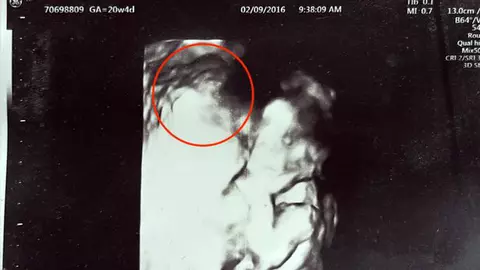

O mamă îndurerată, care și-a pierdut tragic copilul nenăscut, a dezvăluit cum o ecografie pare să o înfățișeze pe Fecioara Maria ținându-i fiul. Cassie Lee a aflat că fătul din pântecul ei a murit în timpul unui control la doctor, după ce medicii nu au reușit să găsească bătăile inimii, la o scanare de 20